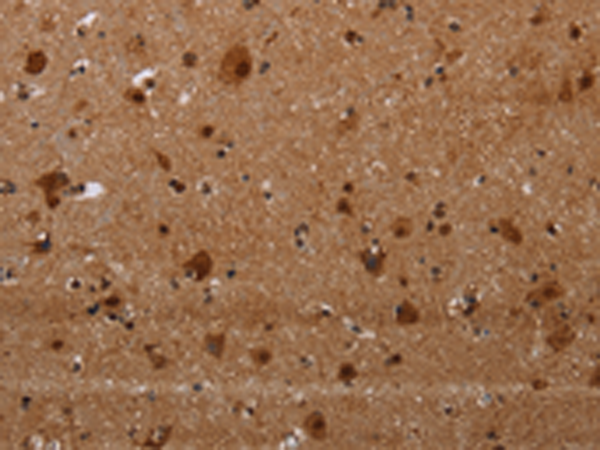

分类: 科研抗体货号: P05023别名: LOR2; WS9-14应用: IHC反应种属: Human, Mouse, Rat